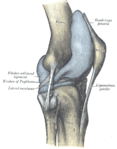

وتتصل عظمة الفخذ والظنبوب (عظمة الساق السفلى الكبيرة) بثلاث طرق هي : 1 – بالأربطة (أنسجة قوية شبيهة بالوتر)، 2 – بالعضلات، 3 - بمحفظة زليلية. وتحيط المحفظة الزليلية بالمفصل. وأربطة الركبة هي الموصلات الأقوى بين عظمة الفخذ والظنبوب. وهذه الأربطة تمنع العظمات من التزحزح عن مكانها.

وتوجد مجموعة معينة من العضلات مسؤولة عن حركة ثني الركبة، بينما تعمل مجموعة أخرى على إبقائها في الوضع المستقيم. وتربط حبال تسمى الأوتار العضلات بالعظام.

يغطي نسيج ناعم يُسمى الغضروف أطراف عظمة الساق وعظمة الفخذ، ويساعد هذا النسيج العظام على الانزلاق بسهولة فوق بعضها بعضًا. وبما أن الغضروف ذو طبيعة منطادية فهو يعمل أيضًا كوسادة.